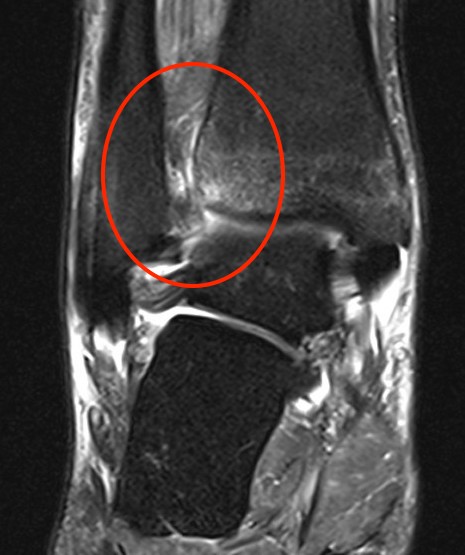

MRI

Tear of AITFL / intact PITFL

Tear of AITFL, intact PITFL, and syndesmotic injury with external rotation of the fibula

Tear of AITFL & PITFL with syndesmotic widening

Sikka MRI classification

Grade I: isolated AITFL

Grade II: AITFL + intra-osseous membrance

Grade III: AITFL + PITFL

Grade IV: AITFL + deltoid ligament